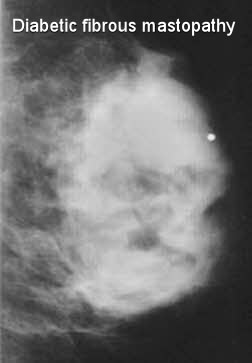

• The mammographic and sonographic features of diabetic mastopathy may be suspicious for malignancy:

• Mammography may reveal an ill-defined mass, distortion, or dense glandular breast tissue

unknown-1diabetic-fibrous-mastopathy-breast-xray72004d613f0fdcb31dd3b59df60c34_big_gallery